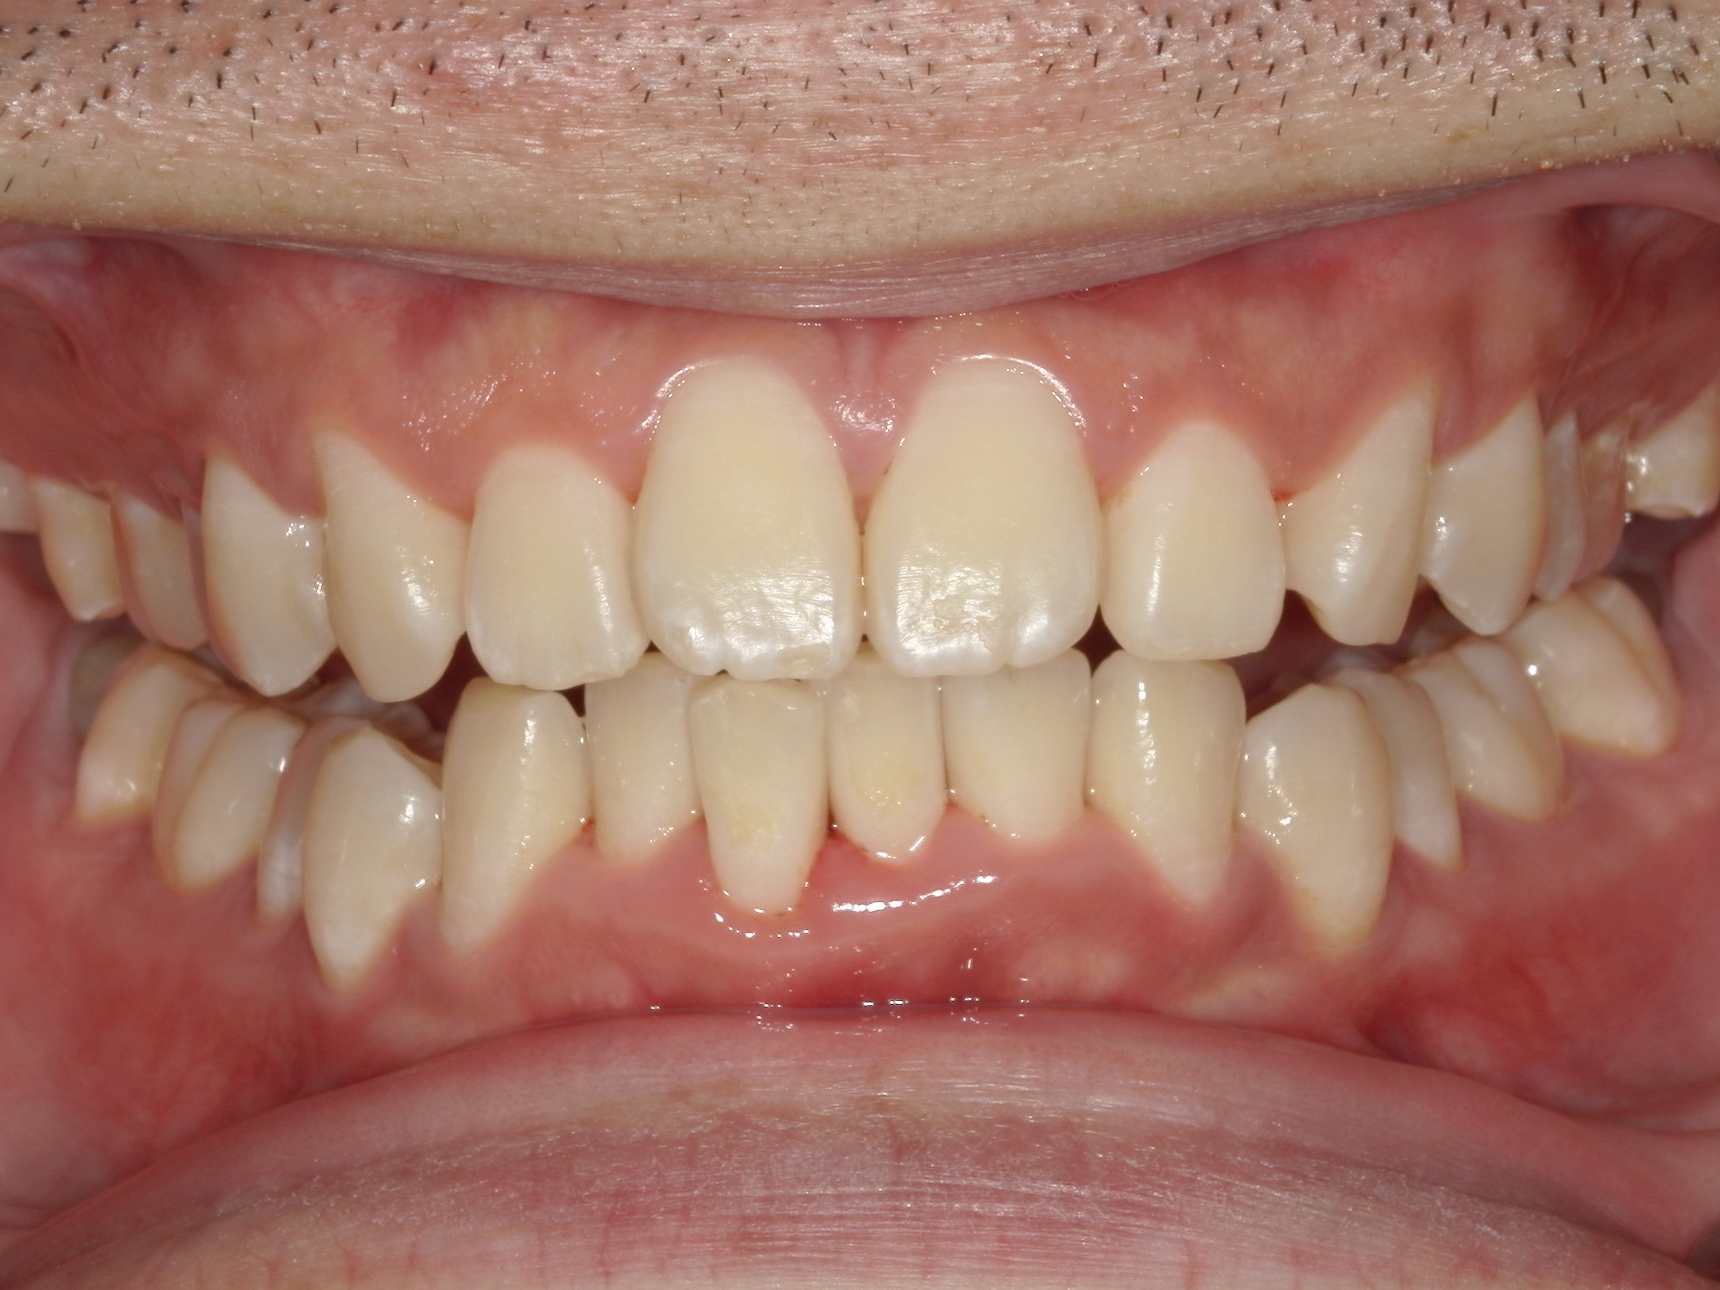

治療後